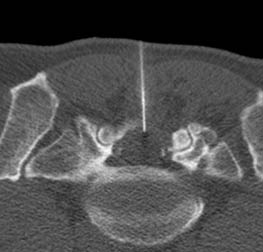

Prima dell'avvento della risonanza magnetica, lo studio tramite mielografia rappresentava l'unico metodo per poter visualizzare direttamente il canale spinale contenuto nello scheletro osseo della colonna vertebrale. Il concetto che sta alla base di questa procedura è l'introduzione, mediante puntura diretta, di un mezzo di contrasto specifico all'interno degli spazi subaracnoidei perimidollari o del sacco durale. In questo modo è possibile visualizzare questi spazi che sono normalmente riempiti di liquido e normalmente non direttamente visibili ai raggi-x. La metodica tradizionale con controlli radiografici e radioscopici viene ulteriormente migliorata dalla possibilità di effettuare una scansione TAC o TC dopo l'introduzione del farmaco: grazie alle apparecchiature attuali è cosi possibile effettuare studi ad altissima risoluzione sul sacco durale , il contenente e il contenuto, in particolare sulle radici nervose e le emergenze delle stesse.

L'esame può seguire iter differenti a seconda del tipo di studio o indicazione clinica. Il paziente può essere seduto lateralmente sul tavolo radiografico oppure disteso in posizione prona sul lettino TC. Il radiologo esegue un reperaggio con immagini ed inserisce un ago spinale nella parte centrale della colonna (può essere utilizzata o meno una piccola anestesia locale). Una volta raggiunto lo spazio subaracnoideo viene iniettato il liquido di contrasto, in seguito vengono effettuate le acquisizioni per immagini.